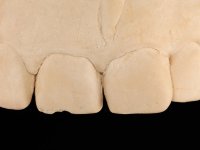

The proposed treatment results from the limitations imposed by the patient, who refused an orthodontical pull of the canine into the edntulous space, and was unwilling to extract the impacted canine and place an implant in the zone of 1.3. Thus, the confection of a Maryland Bridge was proposed, with a Zr infrastructure and two retainers. The mesial retainer would be bonded to the palatal face of the tooth 1.2 and the distal retainer was to be bonded to the palatal wall of tooth 1.4.

To define the dental zone to be covered by the Maryland bridge retainers, the patient was asked to perform maximum intercuspidation movements, and the contact points were marked with articular paper. Tooth preparation of the interproximal surfaces was made, to create a prosthetic insertion axis. It was sought that the mesio-distal diameter at the incisal level was equal to the diameter mesio-distal at the cervical level, that is to say, the interproximal walls were parallelized. Tooth preparation was done with fine grain diamond drills, and later polishing was done with abrasive discs. Color information was collected even before confection of the impression, to avoid dehydration of the arcade. Definitive impression was made using wash technique impression with silicone of heavy and regular consistency, both with fast setting, and a working plaster model was prepared in the lab. A laboratory scanner was used to scan the working model, and later, the infrastructure for the Maryland bridge was made using a CAD-CAM process. Ceramic was placed on this subframe. A ceramic adhesive was applied to the internal surface of the wings and connectors, which would enable bonding to the adjacent teeth. The adhesive bridge was bonded in the mouth following the conventional bonding technique. After bonding, the protrusion and laterality movements were carefully checked to avoid undesirable contacts.